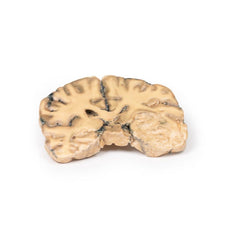

3D Printed Metastatic Carcinoma in the Brain

Pathology

The specimen is the cerebrum sliced horizontally. On the superior view, the right hemisphere is

clearly enlarged, particularly in the parietal region where the gyrae are widened and 3 cystic tumours are

evident. The largest, 5 cm in diameter, is in the right parietal region. A smaller tumour, 2 x 1.5 cm in

diameter, is seen close to the posterior margin of the largest tumour. A third one, 1.5 cm in diameter, is

present in the left parietal region. The tumours have mainly involved white matter. The wall of each lesion is

composed of shaggy friable greyish tissue. At necropsy, there was ulceration of the largest tumour into the

right lateral ventricle (seen more clearly when the inferior surface is examined). Sub-falcine herniation was

also seen, as is displacement of the basal ganglia and internal capsule. Histological examination revealed

metastatic carcinoma in the viable areas. Other metastases were found in the liver and bone. Histology of a

liver metastasis was consistent with origin from a primary carcinoma of breast.